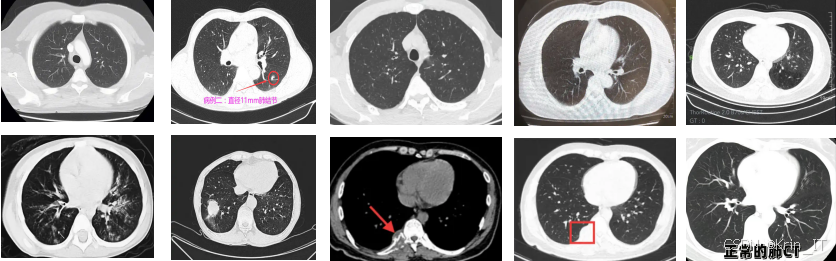

随着医疗影像技术的迅猛发展,计算机断层扫描(CT)已经成为肺部疾病诊断中不可或缺的工具。肺结节,作为肺癌的重要早期指征,其早期发现和准确诊断对提高患者生存率至关重要。然而,传统的肺结节检测方法依赖于放射科医生的经验,受到人为因素的影响,容易出现漏诊或误诊的情况。此外,随着CT图像数据量的增加,人工检测的效率和准确性面临挑战。肺部CT图像肺结节检测算法能够实现对肺结节的自动检测与分类,显著提高了检测速度,减轻了放射科医生的工作负担。深度学习模型能够从海量的CT图像中提取更为细致的特征,提升了对微小结节的识别能力,尤其是在早期肺癌筛查中,能够发现那些肉眼难以识别的病变。

肺部CT影像在一次成像过程中通常会生成几十到上百张图像,这些图像展示了患者在短时间内各个角度的动态CT结果。然而,由于CT扫描仪在肺部运动时,肺结节可能会因为不同拍摄角度而被遮挡,这增加了误诊的风险。在实际检测中,观察到同一患者的CT影像中,呈现的肺结节在大小和亮度上存在明显差异,这些变化主要受到扫描角度的影响。因此,如何在众多CT图像中有效追踪肺结节成为了检测任务的关键。

在图像采集过程中,为确保数据的多样性和代表性,我们采取了一系列有效的措施。首先,选择高分辨率的CT扫描设备,以捕捉肺部细微结构的变化,确保获得清晰、详细的影像。其次,在采集过程中,设置标准化的扫描协议,确保每次扫描的参数一致,从而减少因设备差异导致的影像质量变化。此外,为了增强数据集的多样性,尽可能覆盖不同年龄、性别和病史的患者,确保数据的广泛性和适用性。最后,针对肺结节的不同位置和形态,采用不同的扫描角度和切片厚度,以捕获肺结节在不同状态下的表现。这些措施不仅提高了数据的质量,也为后续的模型训练和评估提供了可靠的基础。